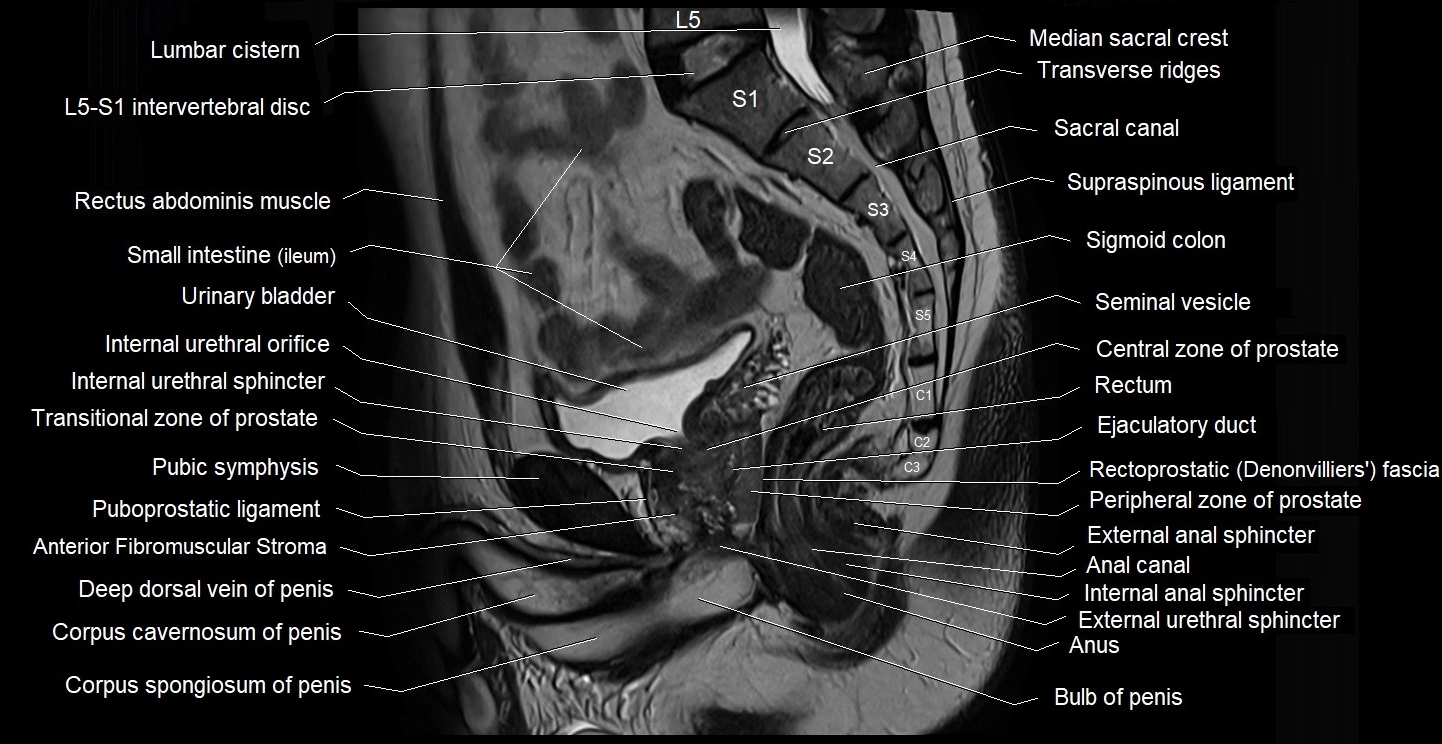

- Anal canal

- Bulb of Penis

- Central zone of prostate

- Corpus cavernosum

- Corpus spongiosum

- Deep dorsal vein of penis

- Ejaculatory duct

- External anal sphincter

- External urethral sphincter (male)

- Internal anal sphincter

- Internal urethral sphincter (male)

- L5–S1 Intervertebral disc

- Median sacral crest

- Peripheral zone of prostate

- Prostatic urethra

- Pubic symphysis

- Puboprostatic ligament

- Rectoprostatic fascia (Denonvilliers' fascia)

- Rectum

- Sacral canal

- Sacral hiatus

- Seminal vesicle

- Sigmoid colon

- Transitional zone of prostate

- Transverse ridges